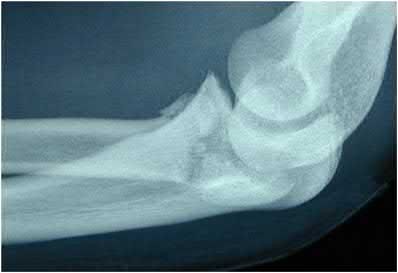

The primary blood supply to the scaphoid is from the dorsal carpal branch of the radial artery, which enters the dorsal ridge of the scaphoid at the waist and courses proximally. This retrograde blood flow makes proximal pole fractures highly susceptible to avascular necrosis and nonunion. The superficial palmar branch provides a minor supply (about 20%) to the distal pole.